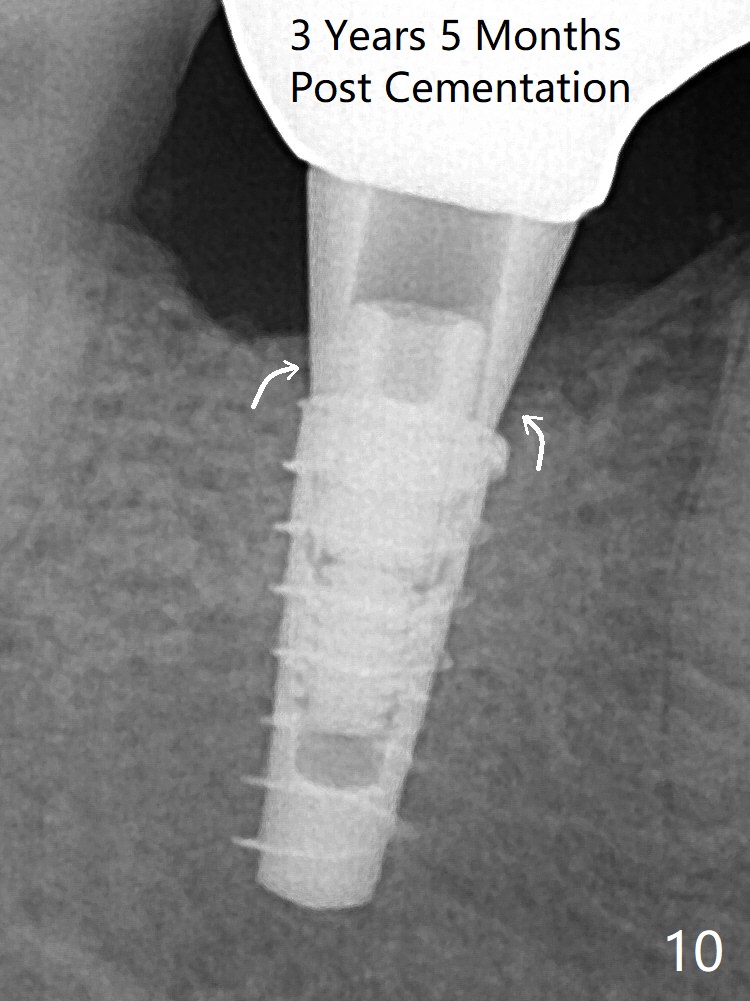

For safety, a 4x9 mm IBS implant is placed with insertion torque 40 Ncm; a 5x5.7(4) mm abutment is immediately placed for an immediate provisional to cover the large socket and keep Vera graft in place (Fig.4 *). Yellow dashed line: apical osteotomy; red dashed line: Mental Loop. Impression is taken nearly 3 months postop (Fig.6). The bone density around the implant increases 7 months post cementation (Fig.8 *). The higher density bone seems to extend coronally 1 year 7 months post cementation (Fig.9). The dense bone apparently extends toward the abutment as well 3 years 5 months post cementation (Fig.10 curved arrows).